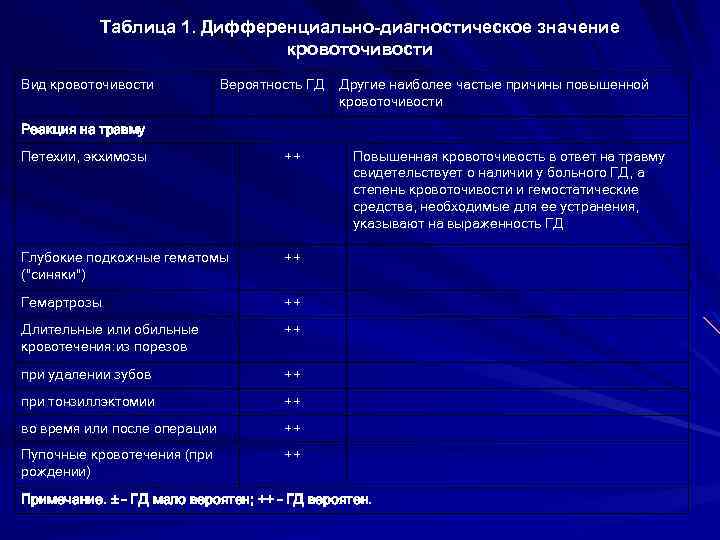

Дифференциальная диагностика заболеваний плевры